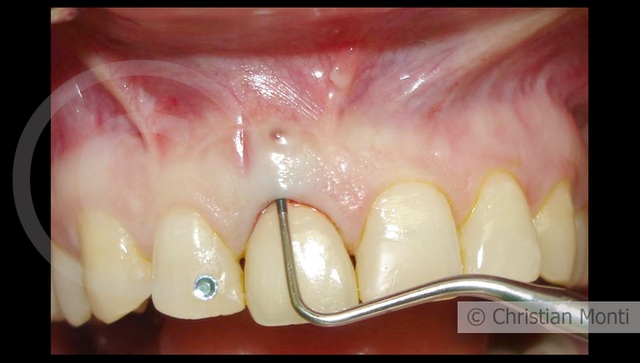

EDENTULIA SINGOLA

Impianto in sostituzione di un incisivo superiore